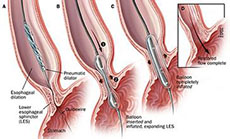

肝胆胰腺疾病治疗方法

疾病介绍:1.腹腔镜手术:我科已开展腹腔镜胆囊切除术,腹腔镜胆道探查取石术,阑尾切除术。对于常规行开腹手术的疾病,目前我科也已开展腹腔镜手术治疗,如:腹…【详细】